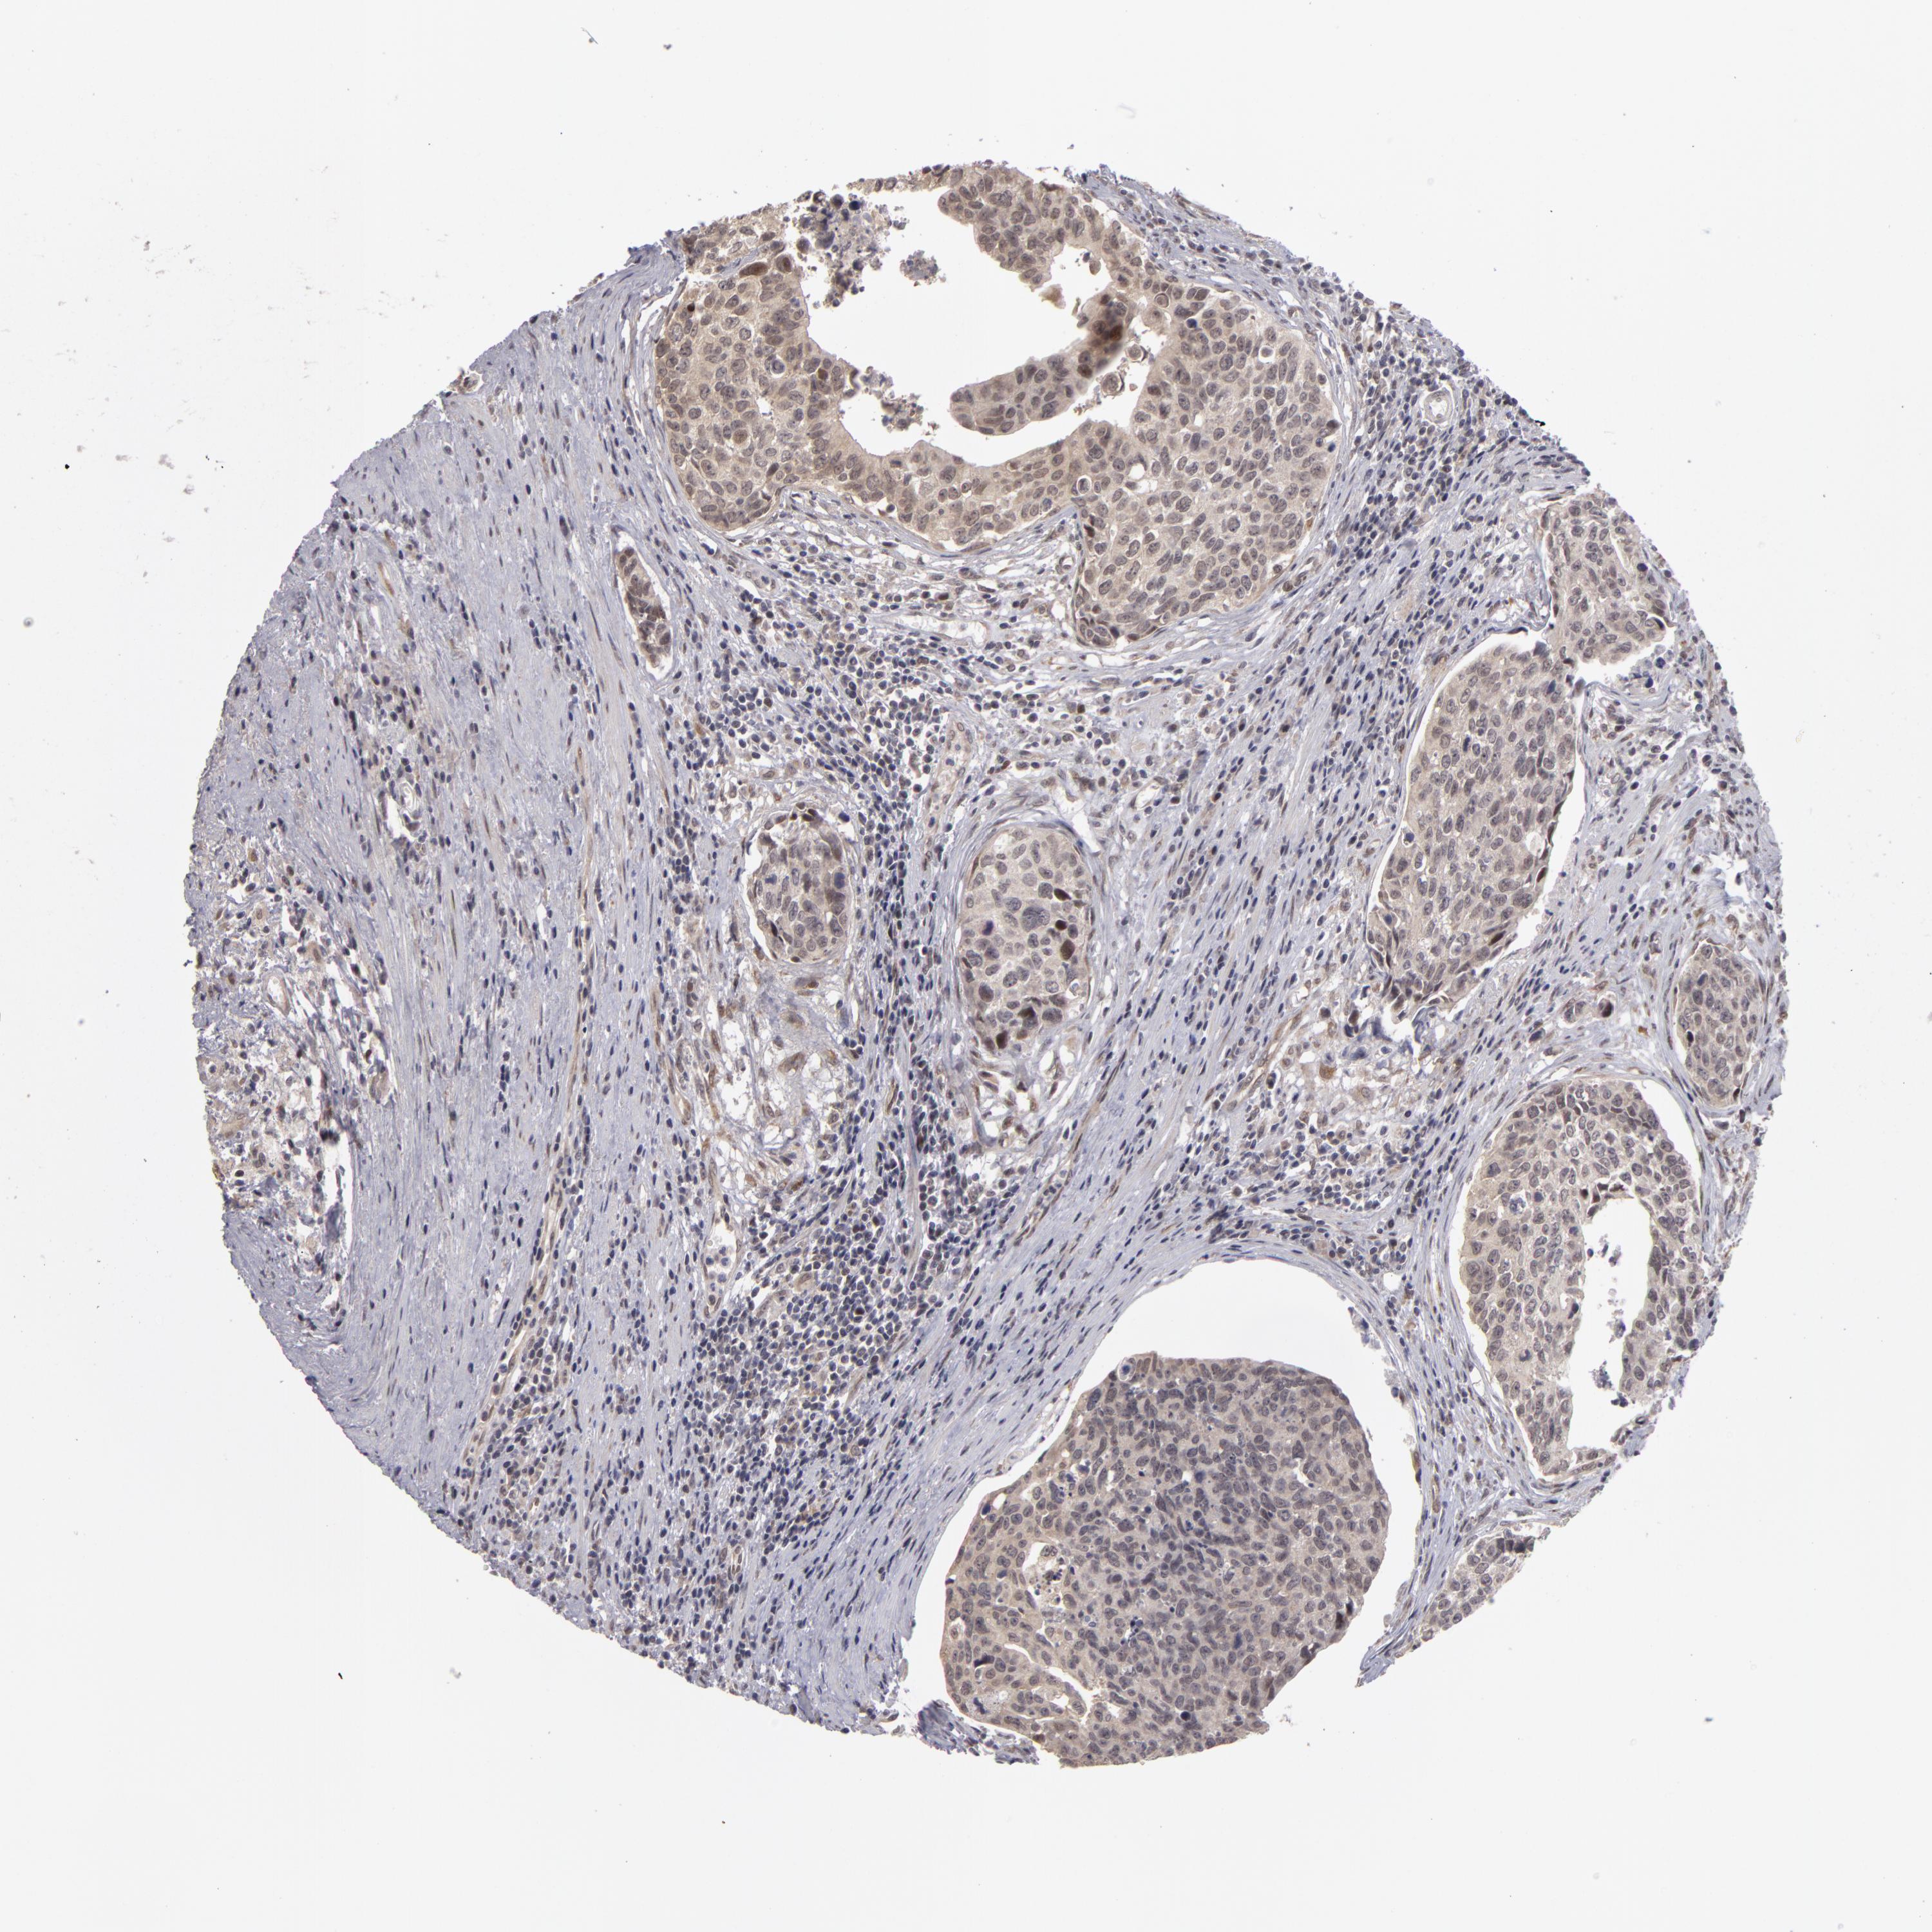

UROTHELIAL CANCER - Protein expressioni

A mouse-over function shows sample information and annotation data. Click on an image to view it in a full screen mode. Samples can be filtered based on level of antibody staining by selecting one or several of the following categories: high, medium, low and not detected. The assay and annotation is described here.

Note that samples used for immunohistochemistry by the Human Protein Atlas do not correspond to samples in the TCGA dataset.

Antibody stainingi

Antibody staining in the annotated cell types in the current human tissue is reported as not detected, low, medium, or high, based on conventional immunohistochemistry profiling in selected tissues. This score is based on the combination of the staining intensity and fraction of stained cells.

Each image is clickable and will lead to virtual microscopy that enables deeper exploration of all samples and also displays staining intensity scores, fraction scores and subcellular localization as well as patient and tissue information for each sample.

Antibody HPA001493

Staining

High

Medium

Low

Not detected

Intensity

Strong

Moderate

Weak

Negative

Quantity

>75%

75%-25%

<25%

None

Location

Nuclear

Cytoplasmic/membranous

Cytoplasmic/membranous,nuclear

Urothelial carcinoma, Low grade